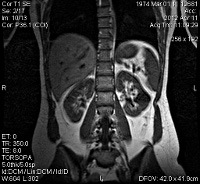

MRI of abdominal organs.

МРТ брюшной полости и забрюшинного пространства. Техника неинвазивной визуализации внутренних органов брюшины и забрюшинного пространства. В отличие от КТ и рентгеновских лучей, МРТ не поддерживает облучение, а воздействие на организм достигается внешним магнитным полем. Исследование этой области может включать МРТ печени, желчных протоков, поджелудочной железы, кишечника, мочевыделительной системы, надпочечников, брыжеечных сосудов, тщательное изучение структур брюшной полости. Диагностические возможности исследования чрезвычайно широки - это выявление пророков развития, воспалительных заболеваний, ран, органических поражений, источника кровотечений из желудочно-кишечного тракта, холедохолитиаза и стриктур желчных путей.

МРТ брюшной полости. Неинвазивная диагностическая процедура, основанная на получении информации путем декодирования радиомагнитных импульсов, излучаемых атомными ядрами во внешнем магнитном поле. Это позволяет создавать трехмерные изображения паренхиматозных и полых органов, лимфатических узлов, кровеносных и лимфатических сосудов. Используется для оценки размеров и формы внутренних органов, определения локализации, распространенности и типа патологических процессов.